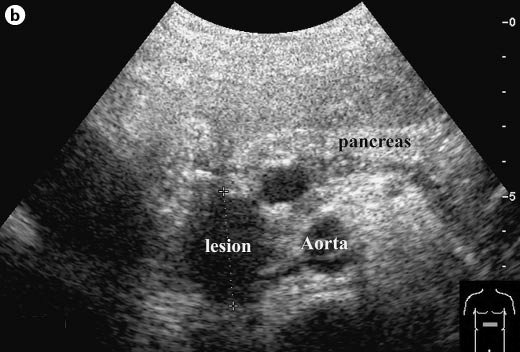

3. kép:

A vese ultrahangos képe

Ezen a képen a vese sematikus ábrája és mellette az ultrahangos képe látható.